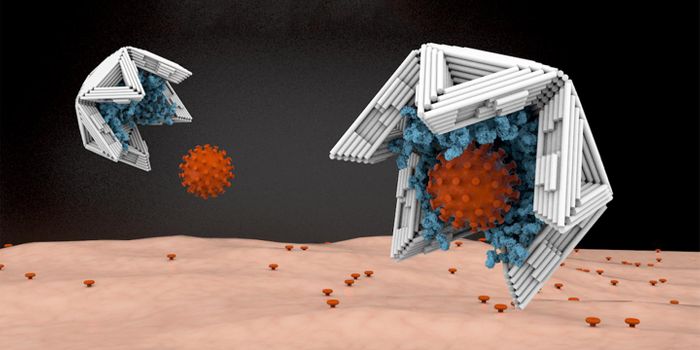

FEB 25, 2015Health & MedicineWith antibiotic resistance on the rise, scientists are looking for innovative ways to combat bacterial infections. The p ...

MAY 15, 2022MicrobiologyIn a clinical first, reported in Cell, researchers used viruses that infect bacteria, called bacteriophages or phages fo ...